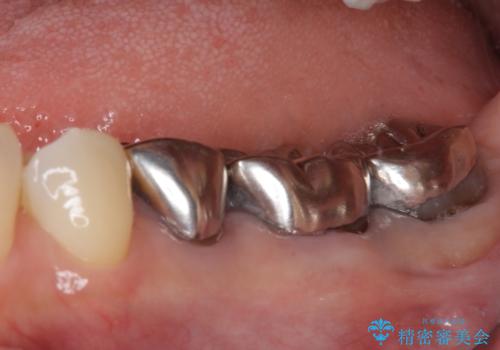

- 近医にて奥歯の抜歯が必要と言われたとのことで来院された患者様です。

診断の結果、奥歯は歯根が破折しており、抜歯が必要な状況でした。

インプラントあるいはブリッジによる補綴治療が考えられましたが、前後の歯が大きな銀歯であったため、オールセラミックブリッジにより3本の歯を審美的に仕上げることとしました。